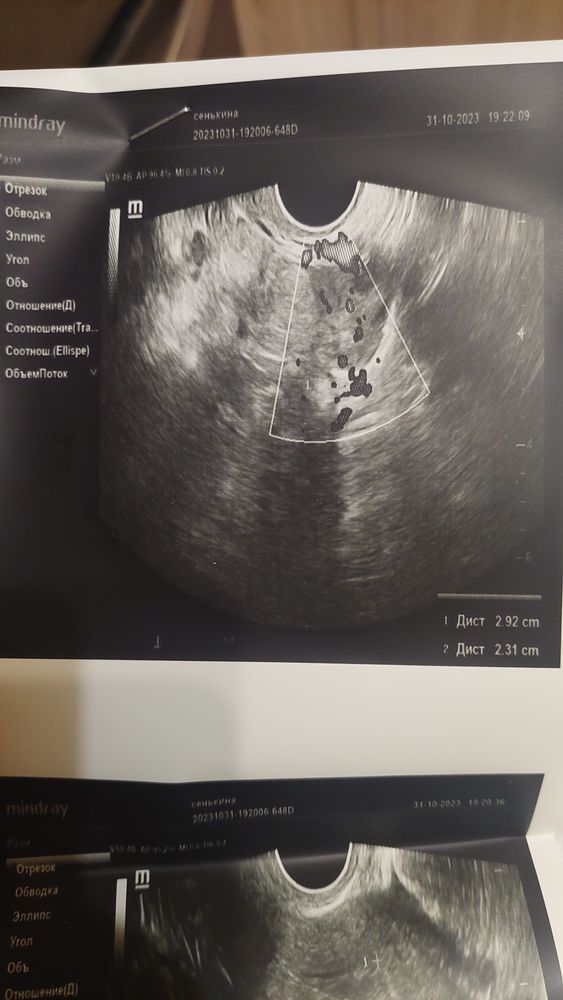

Снимок крайне забавный, я впервые увидела все это дело на узи 😄

Эндометрий хороший, жёлтое тело 11.3 мм ❤️